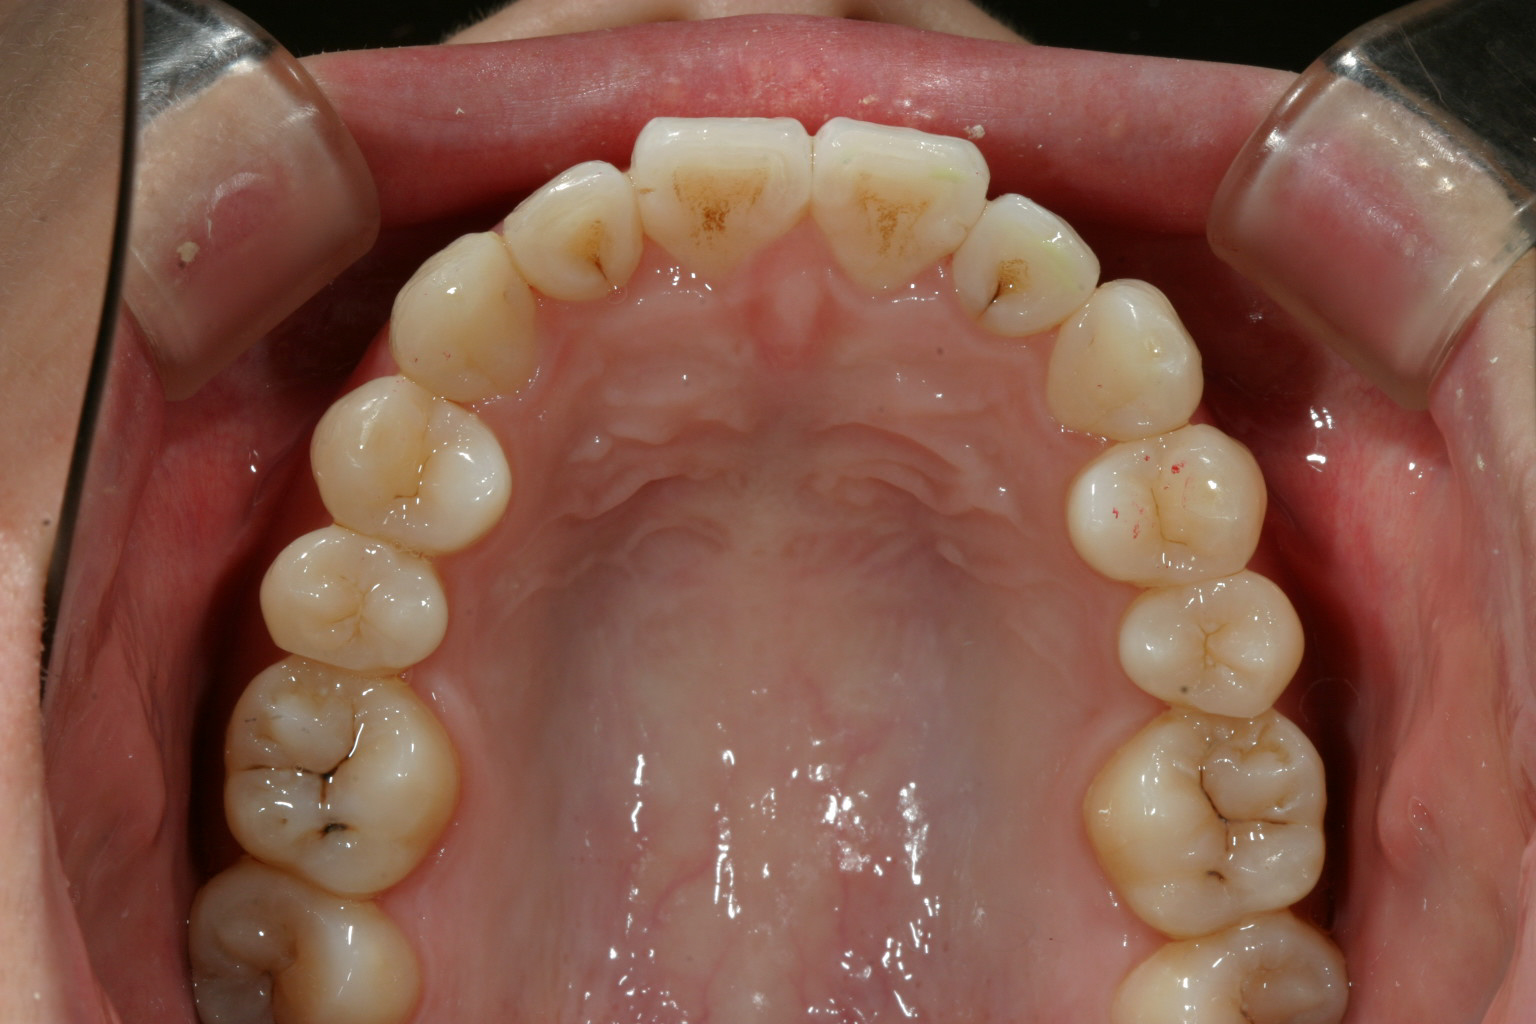

綺麗に改善しました。

下顎のガタガタも綺麗に改善しました。

オーバージェットも綺麗になっています。